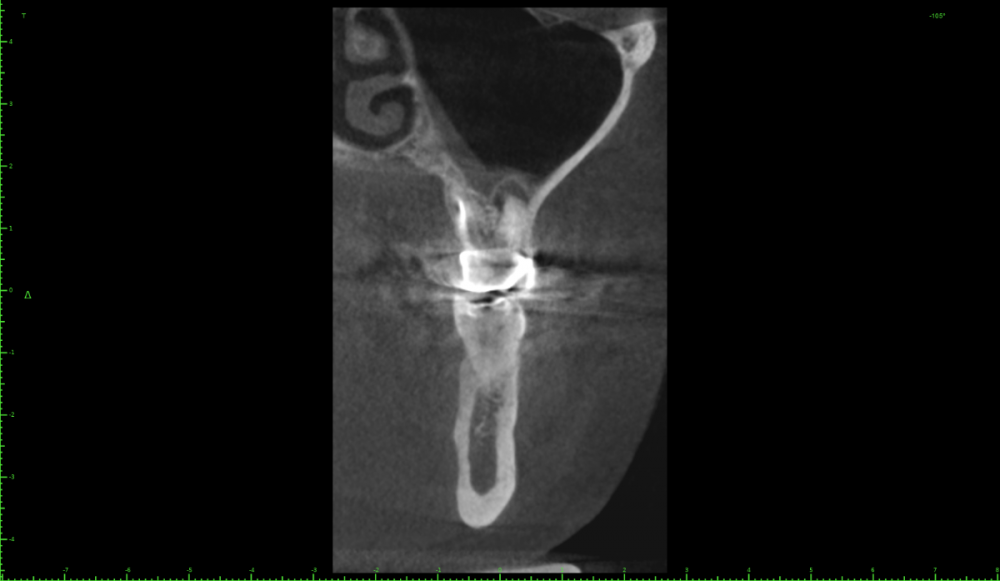

Katya88 Опубликовано 28 июля, 2021 Поделиться Опубликовано 28 июля, 2021 Мой стоматолог терапевт советует удалить, так как там кисты, а ортопед советует найти того, кто займется лечением. КТ прилагаю https://drive.google.com/file/d/1Z-neEH63BszTXxa8bAOG1tgsrIrsqrVK/view?usp=drive_web Ссылка на комментарий

Женька Опубликовано 28 июля, 2021 Поделиться Опубликовано 28 июля, 2021 2.6 2.7 3.7 На 3.5 и 1.5 стоит обратить внимание 1.5 1 Ссылка на комментарий

Женька Опубликовано 28 июля, 2021 Поделиться Опубликовано 28 июля, 2021 54 минуты назад, Katya88 сказал: 1.5 менять коронку как минимум снять существующую конструкцию и посмотреть клинически на зуб(ы). 1.5 на КТ выглядит удручающе. По остальным, я бы поддержал ортопеда и попытался зубы сохранить. Пусть коллеги меня поправят. 1 1 Ссылка на комментарий